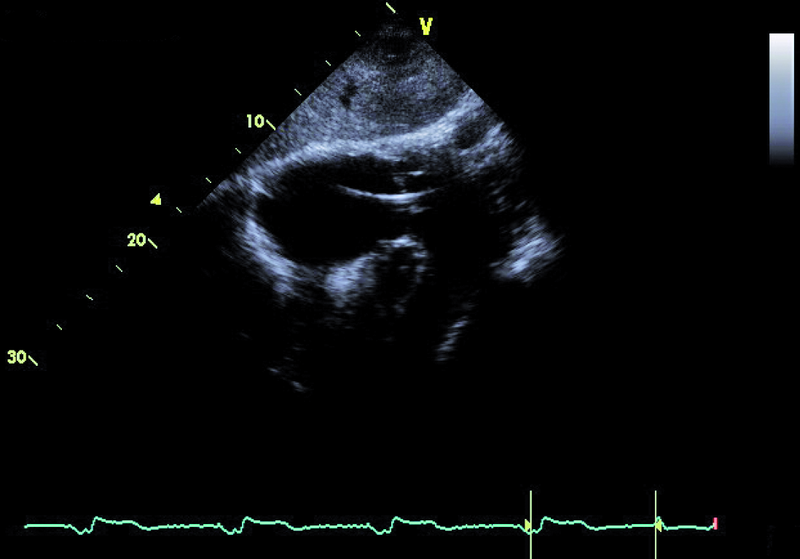

Mężczyzna, lat 59. Jakie patologie można rozpoznać na rycinach?

1. Powiększenie jamy lewego przedsionka (ryc. 1).